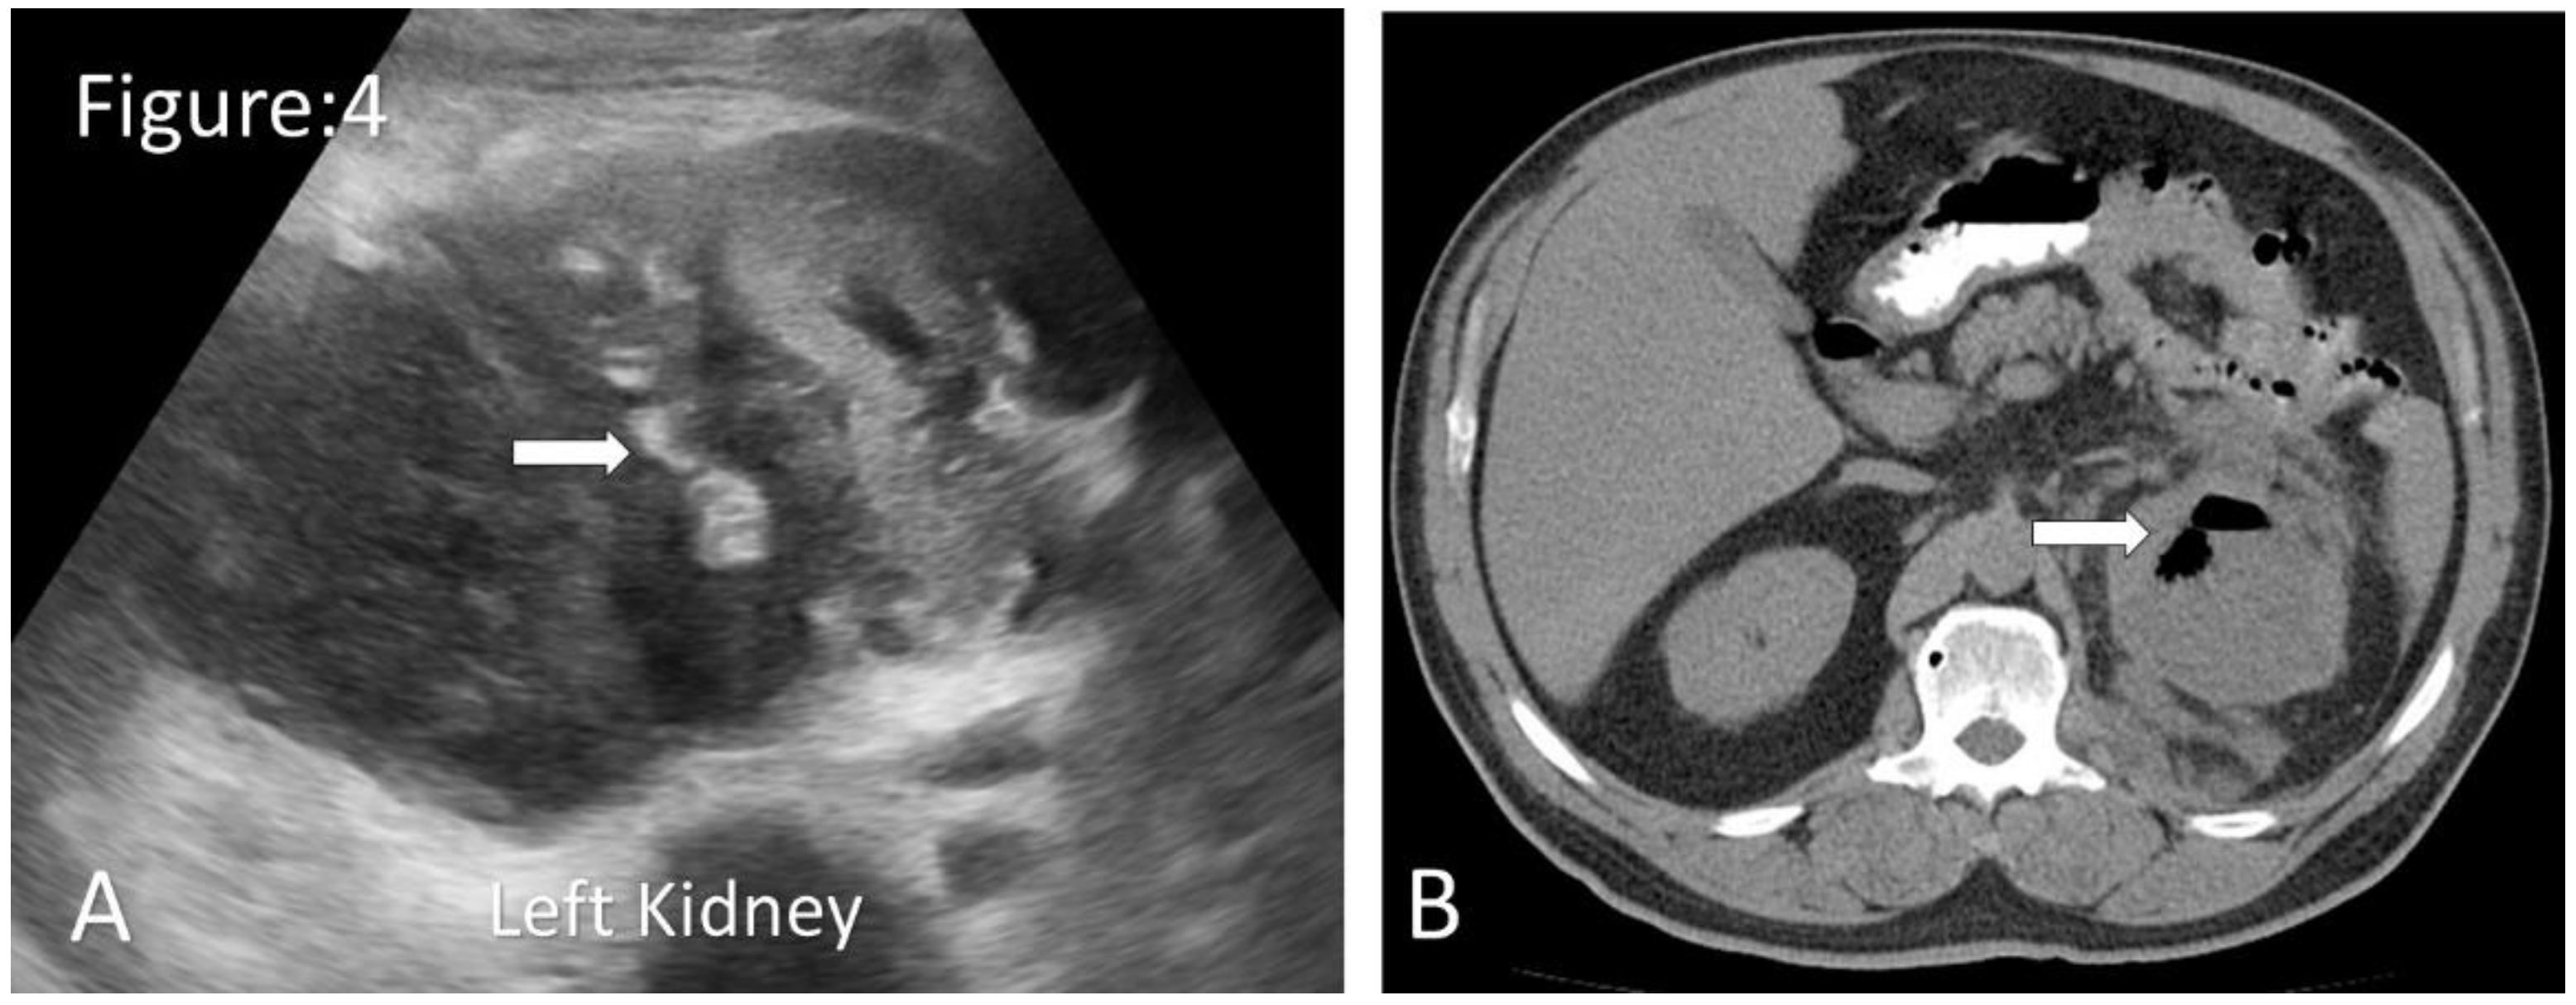

Emphysematous Pyelonephritis.

- Ubee, S.; McGlynn, L.; Fordham, M. Emphysematous pyelonephritis. BJU International. 2011, 107, 1474–1478. [Google Scholar] [CrossRef]

- Narlawar, R.; Raut, A.; Nagar, A.; Hira, P.; Hanchate, V.; Asrani, A. Imaging features and guided drainage in emphysematous pyelonephritis: a study of 11 cases. Clinical Radiology. 2004, 59, 192–197 . [Google Scholar] [CrossRef]

- Grayson, D.E.; Abbott, R.M.; Levy, A.D.; Sherman, P.M. Emphysematous Infections of the Abdomen and Pelvis: A Pictorial Review. Radio Graphics. 2002, 22, 543–561 . [Google Scholar] [CrossRef]

- Gonçalves, E.; Maia, B.T.; Versiani, C.M.; Mota, C.T.; Filho, A.G.S. Pielite enfisematosa unilateral: relato de caso. Radiologia Brasileira. 2013, 46, 56–58 . [Google Scholar] [CrossRef]

- Huang, J.; Tseng, C. Emphysematous Pyelonephritis. Archives of Internal Medicine. 2000, 160, 797. [Google Scholar] [CrossRef]

- Hsu, C.-K.; Wu, S.-Y.; Yang, S.-D.; Chang, S.-J. Emphysematous pyelonephritis: classification, management, and prognosis. Tzu Chi Medical Journal. 2022, 34, 297. [Google Scholar] [CrossRef] [PubMed]

| Classification | Radiological Features Based on CT Findings |

|---|---|

| Class 1 | Gas in the collecting system only |

| Class 2 | Gas in the renal parenchyma without extension to the extrarenal space |

| Class 3A | Extension of gas or abscess to the perinephric space |

| Class 3B | Extension of gas or abscess to the pararenal space |

| Class 4 | Bilateral EPN or a solitary kidney with EPN |